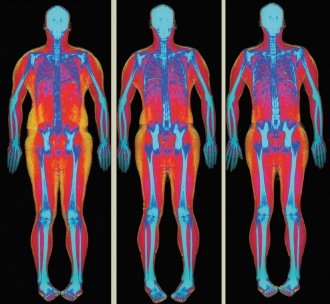

Pierderea în greutate (25)

Metabolism (10)